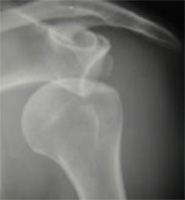

On réalise une radiographie standard d’épaule.

Radiographie de l’épaule

Cette radiographie permet de voir l’usure du cartilage et les déformations osseuses liées à l’arthrose : ostéophytes ou géodes (en jaune sur la photo précédente).

La radiographie permet également de confirmer le diagnostic de la cause de l’arthrose (polyarthrite rhumatoïde, nécrose, rupture massive de la coiffe). On réalisera également un scanner dans le cadre d’un bilan préopératoire pour juger de la quantité d’os restant afin d’y implanter une éventuelle prothèse. L’IRM ou arthro-TDM peut-être utile pour juger de la qualité des tendons de la coiffe des rotateurs.